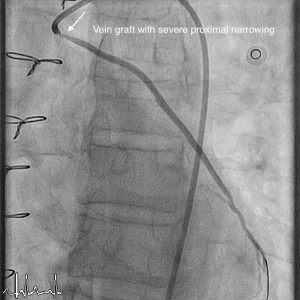

Vein grafts are used during bypass surgery to bypass the blood flow through narrowed coronary arteries. These are mostly taken from leg and used in the heart. Over a period of time, the vein grafts itself can get narrowed and cause chest pain. An angiogram of the graft will confirm this and this may require intervention in the form of angioplasty. Vein graft angioplasty is challenging, as the walls of veins are different from arteries. There is also high risk of clots going down the graft during ballooning process. This requires expertise and also special devices to prevent this happening and to get good result from angioplasty.